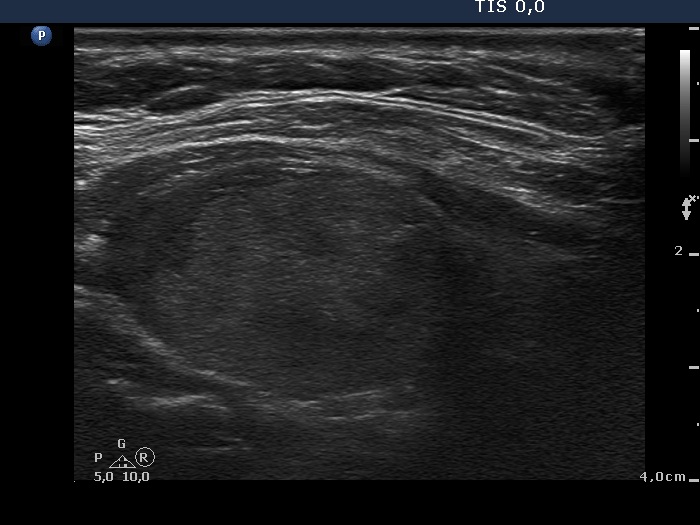

Ultrasonography. Almost the entire right lobe was composed of a minimally hypoechogenic nodule presenting perinodular blood flow. There was a central-type cyst in the left lobe with moderately hypoechogenic solid part. Both the solid and the cystic areas contained large and thick hyperechogenic lines and granules.

Cytology was performed form both lesions and resulted in colloid goiter and cystic lesion, right and left nodule, respectively. We removed 20 mL yellow fluid from the left lesion.

Comment. The intranodular hyperechogenic figures are unusually large. The ventral ones correspond correspond to thickened connective tissue and/or to large aggregates of colloid crystals (comet-tail artifacts) while those located in the back wall of the cyst are caused by posterior acoustic enhancement.